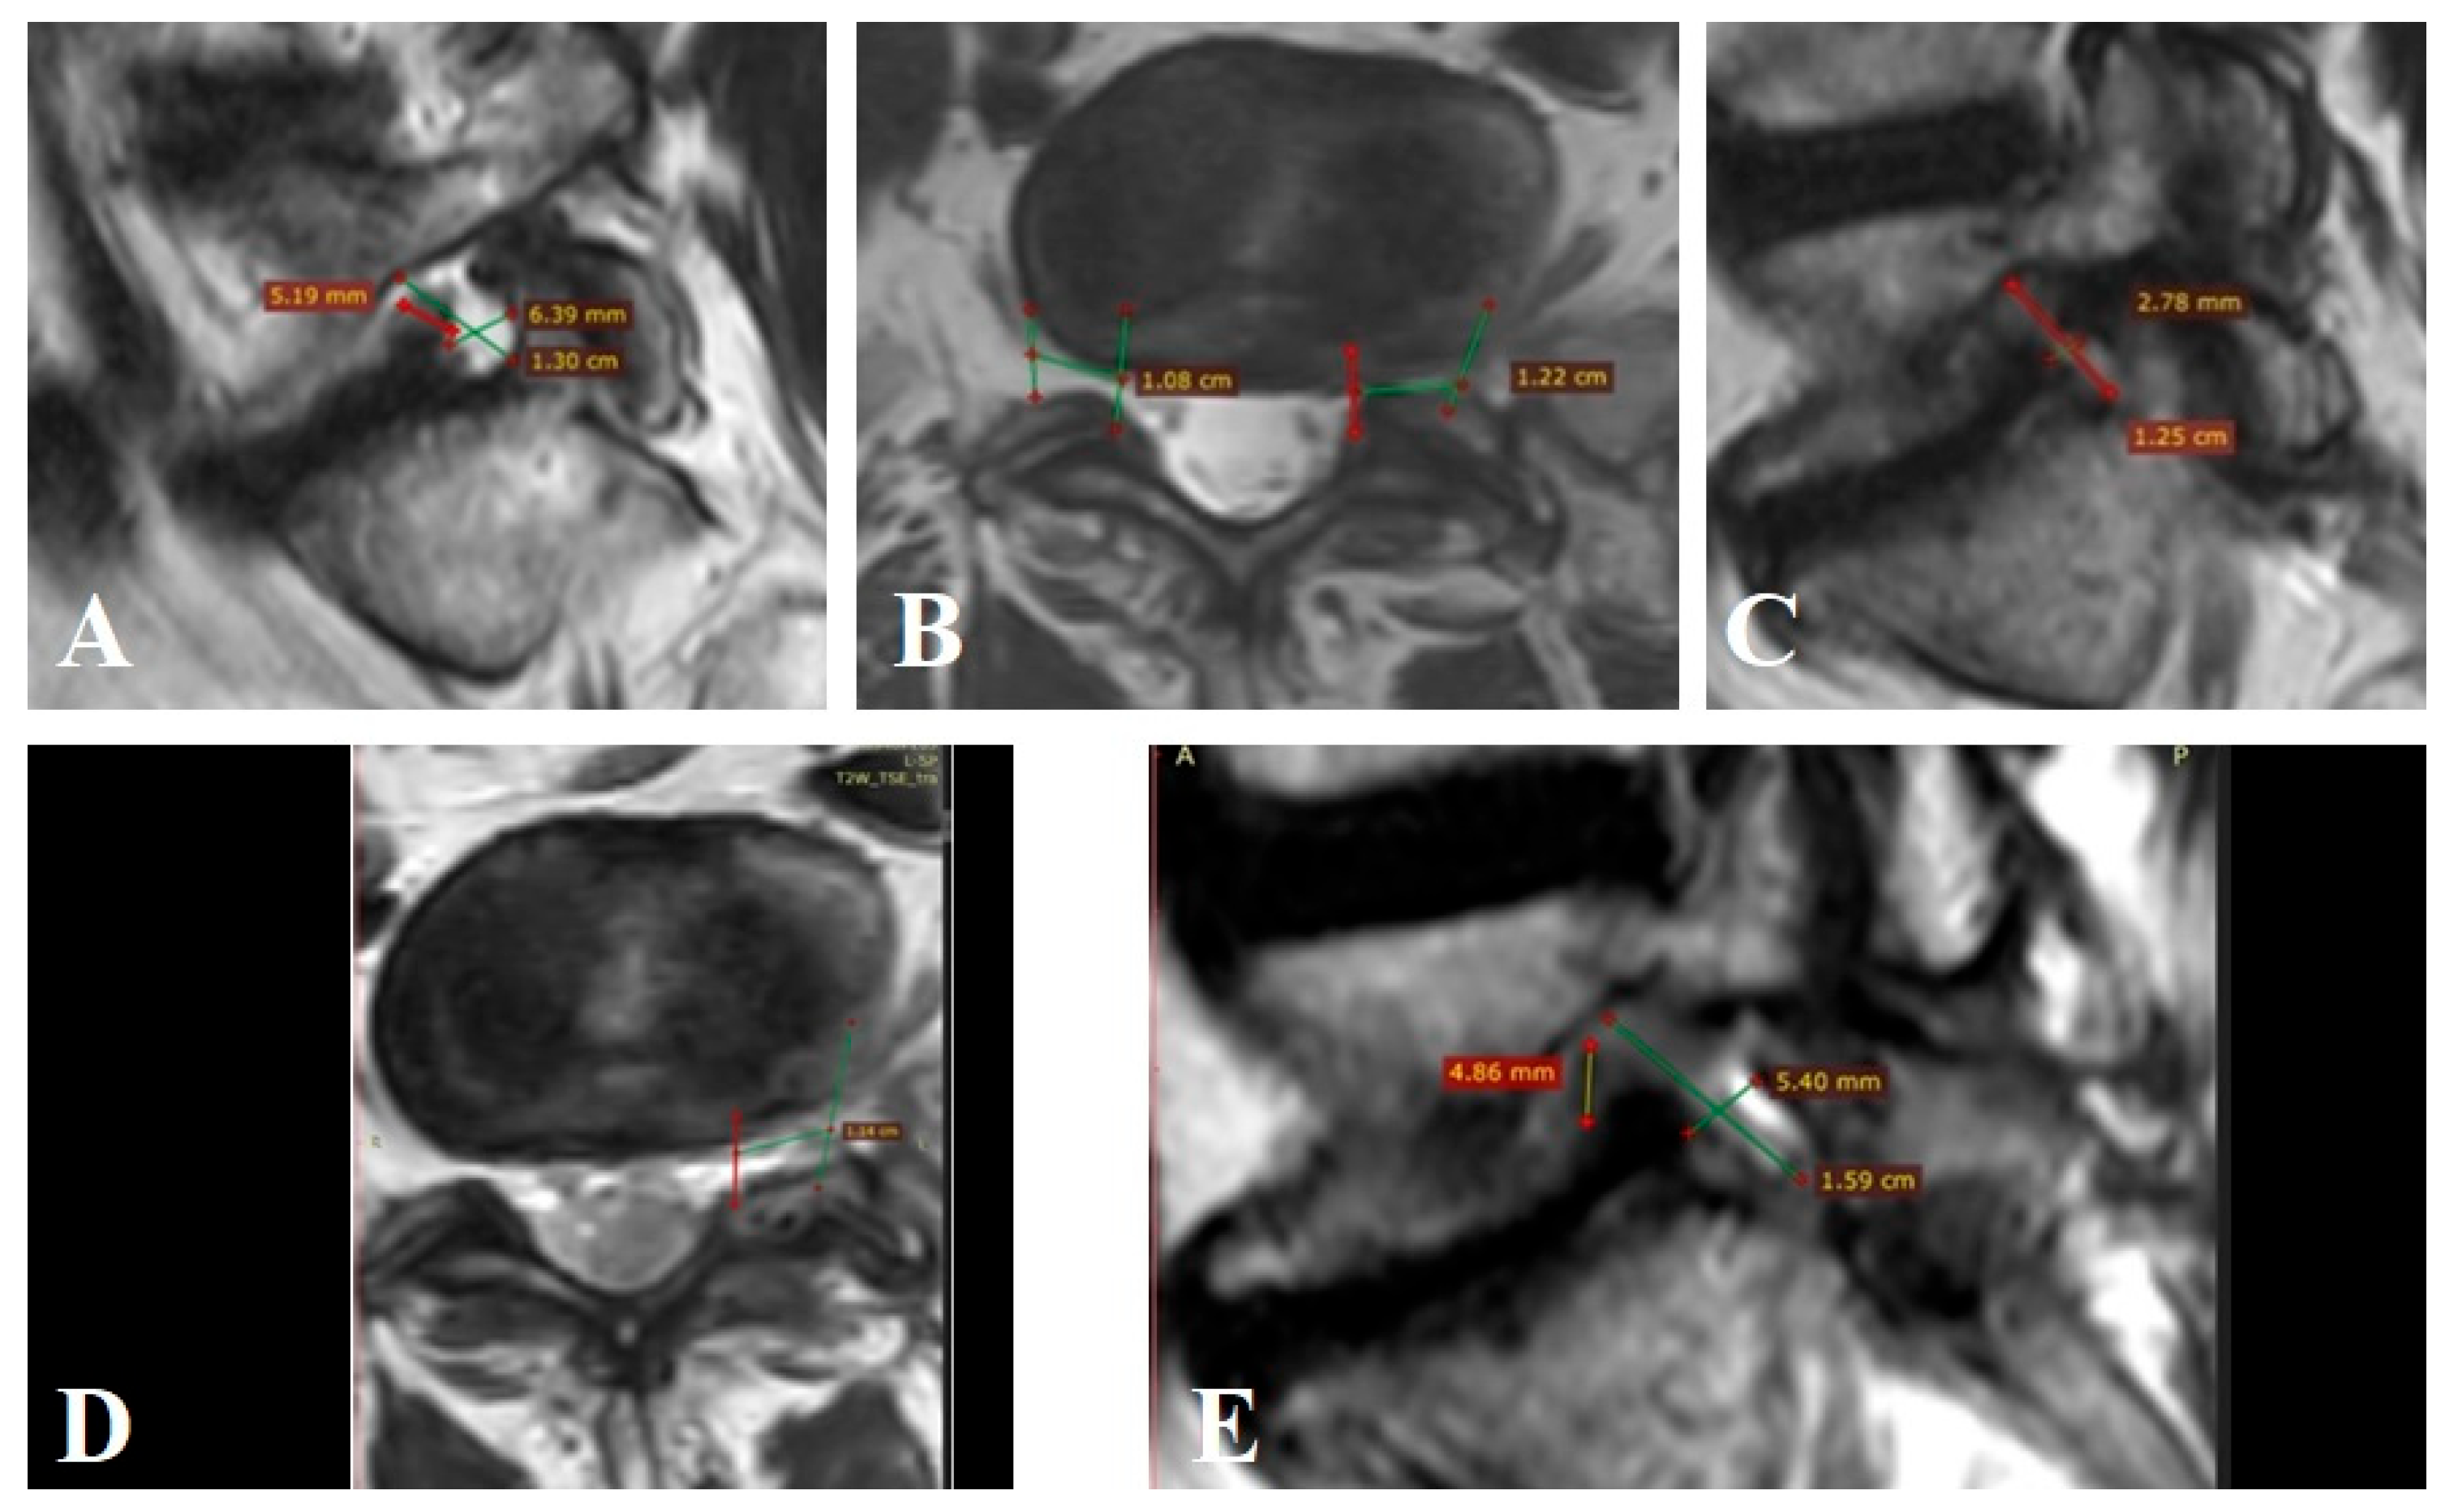

Patient n° 3 is a 35-year-old male, presented with episodic severe lumbar pain radiating to the left lower limb along the L5–S1 dermatome. Pain had persisted for more than three months despite conservative therapy. VAS was 8 cm in the leg and 5 cm in the back, and ODI was 54. MRI showed bilateral foraminal stenosis with moderate degenerative changes: Pfirrmann Grade I–II discs and Fujiwara Grade I–II facet joints. Clinical instability was 5 points per White–Panjabi. On MRI, FC volume at L5–S1 on the left was 412.3 mm3 with nerve volume of 297.1 mm3 (occupancy: 72.1%) (Figure A3A–C). On the right, FC volume was 227.8 mm3 with a nerve volume of 218.2 mm3 (occupancy: 95.7%) (Figure A3A,B). The patient underwent a preperitoneal approach with disc resection and total disc arthroplasty at L5–S1 (ALIF). Postoperatively, indirect bilateral foraminal decompression was achieved. Right FC volume increased to 2003.6 mm3 (occupancy: 10.9%) (Figure A3D,E), a 79.4% increase. Left FC volume increased to 1764.8 mm3 (occupancy: 16.8%) (Figure A3E,F), a 76.6% increase. VAS scores improved to 2 cm (back) and 1 cm (leg). ODI at 12 months was 17.

Figure A3.

MRI of patient n° 3.